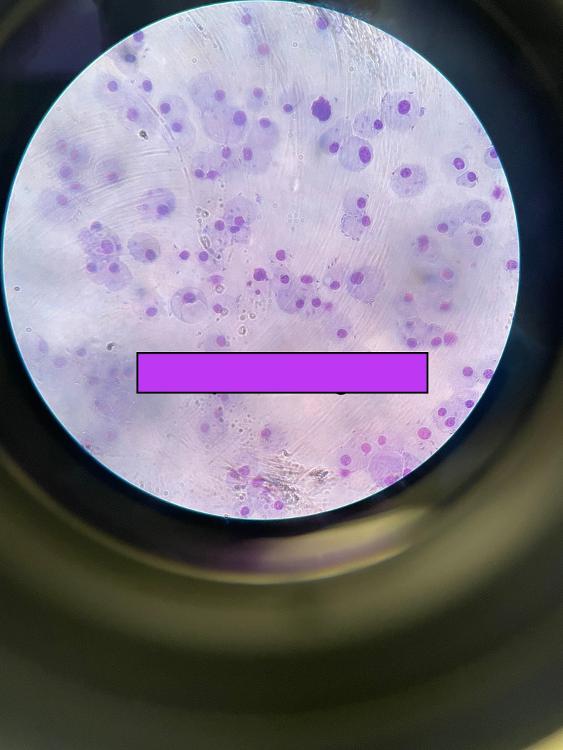

Giardia cysts

Candida

Toxoplasma gondii